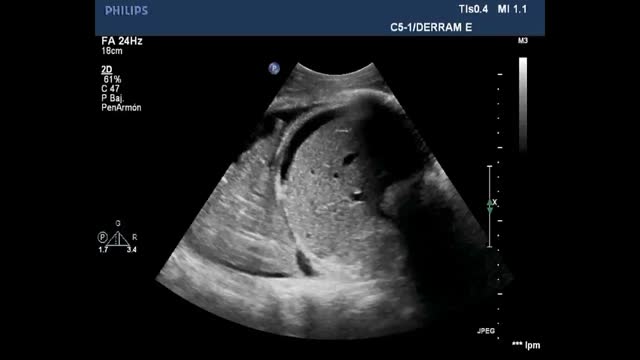

Air does not conduct ultrasoundTherefore, if the lung is ventilated below the pleural line, we will only see artifacts. If otherwise, we observe the true anatomical image, as in pneumonic consolidation or effusion with lung collapse (Suppl. Fig. 1).5

Air/fluid ratioThe different ultrasound patterns reflect a different air/fluid ratio (Fig. 3).5

Alveolar-interstitial syndrome (AIS)The relationship between the gas and fluid contents determines the images observed in lung ultrasound (Fig. 3), and these images change quickly during the clinical course of the patient. In this regard, AIS explored by ultrasound exhibits different patterns that reflect different underlying causes.